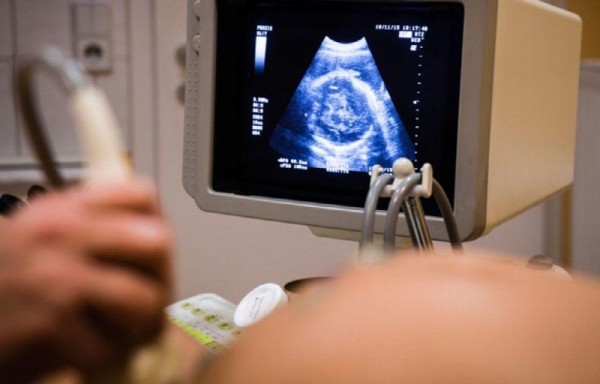

Semanas después fue ingresada en el hospital Ad-Din con dolores en la parte inferior del abdomen, luego de una ecografía los médicos descubrieron que estaba embarazada de mellizos.